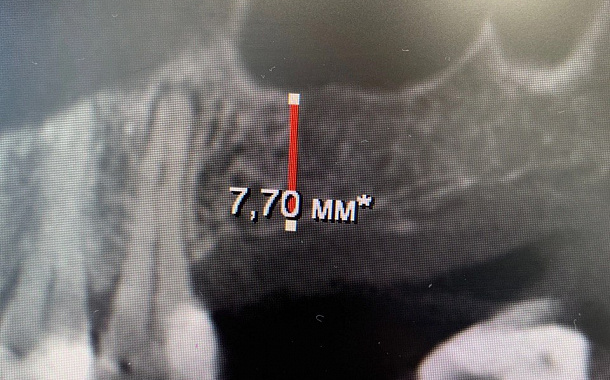

- Есть достаточный для установки имплантата объем костной ткани гребня альвеолярного отростка.

По 3D компьютерной томографии определяет возможность установки имплантата, немедленной фиксации временной коронки в день операции и объем пластических манипуляций. Совместно с врачом-стоматологом ортопедом планирует вид ортопедической конструкции и положение имплантата.

Компьютерная томография в формате 3D - важный диагностический инструмент стоматолога. На полученном объемном снимке стоматолог видит все нюансы вашей зубочелюстной системы: состояние костной ткани челюстей, зубов и височно-нижнечелюстного сустава. Именно томография позволяет доктору составить план и объем предстоящего оперативного вмешательства.